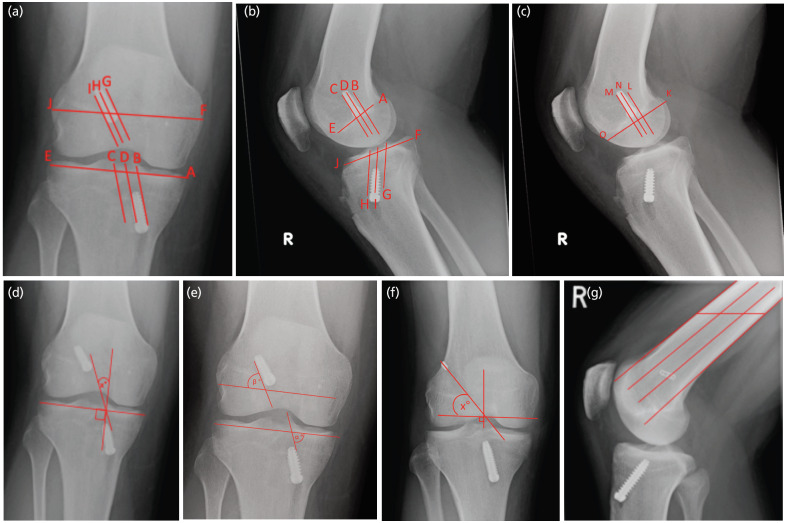

Materials and methods: The patient responses from six patient-reported outcome measures (PROM) at initial presentation and one year following ACLR, as well as demographic data at presentation, were collected. Graft tunnel placement was evaluated using 10 validated radiological measurements on antero-posterior and lateral radiographs following surgery.

Results: A total of 45 patients were included in the study. There was a significant longitudinal improvement (p<0.001) for almost all PROM scores when comparing pre-operative to post-operative results. Overall, no significant correlation was demonstrated between graft tunnel placement and PROM scores, except for a weak association between femoral tunnel positioning on lateral view radiographs and the overall Knee injury and Osteoarthritis Outcome Score (rho=0.37, p=0.038) and the Lysholm score (rho=0.36, p=0.034) and also tibial tunnel placement on lateral view radiographs and the EQ-5D VAS score (rho=0.37, p=0.037).